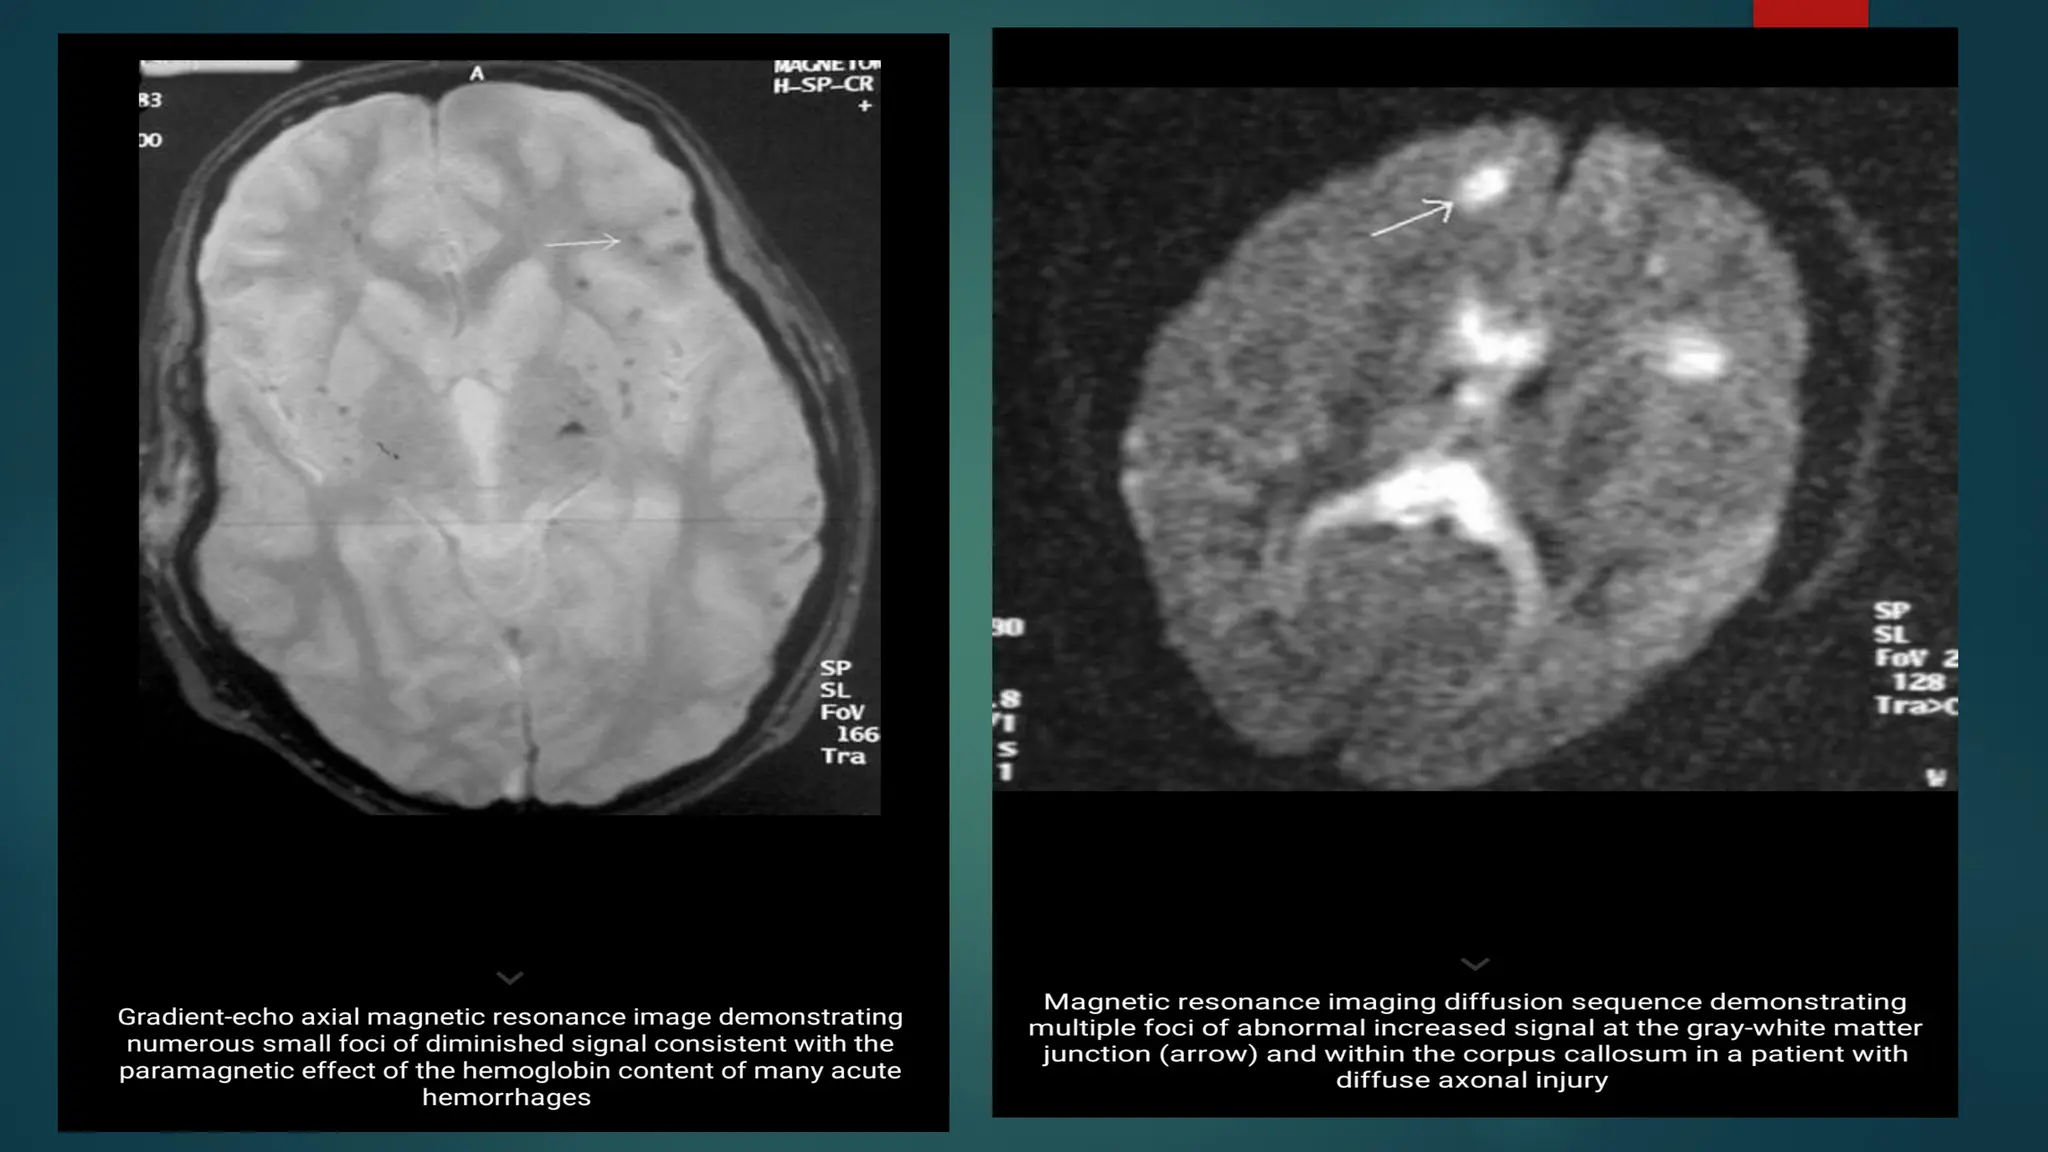

MRI

 Conventional MRI (cMRI) has a higher sensitivity in demonstrating lesions in the

brainstem and the deep white matter, making it more sensitive for identifying

axonal injury compared to CT

 The MRI gradient echo sequence (GRE) is able to detect heme and heme

breakdown products making it a suitable method for discovering small

hemorrhagic lesions.

 Diffusion weighted imaging can accurately examine non haemorrhagic lesions.

High signal DWI can be used in patient with early stage TAI . Lesions found

represent cellular swelling and cytoxic edema.